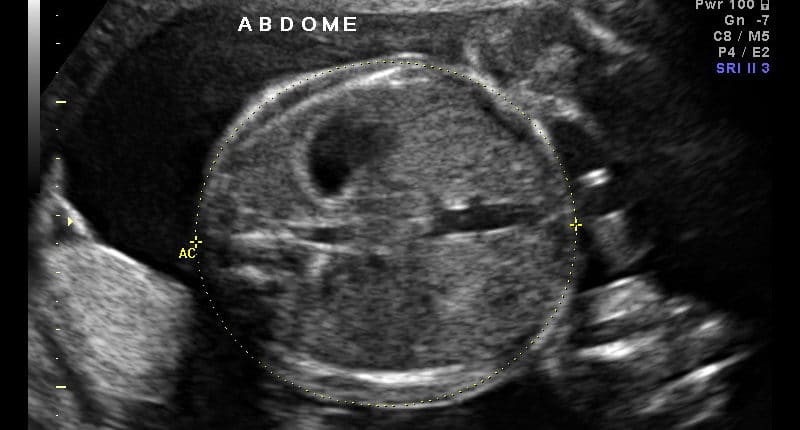

Ultrassom Medida do Abdômen Fetal

Intervalos de Referência Relações Biométricas Fetais

Ultrassom Abdome Fetal

Tórax e Abdome

Tabelas

20/02/2011   7648 Views

Intervalos de Referência da Circunferência Abdominal e Circunferência Torácica Intervalos de Referência da Medida do Diâmetro Longitudinal Renal Fetal